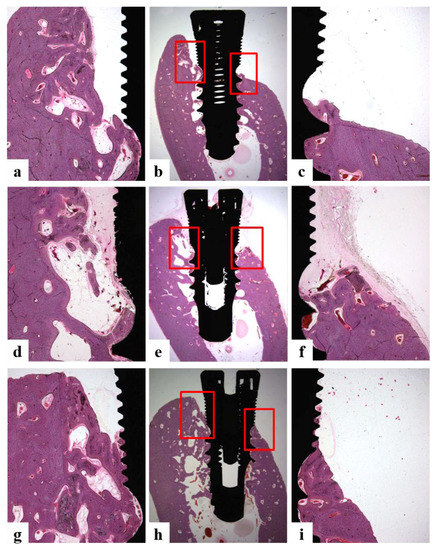

2.5.6. Histologic and Histometric Analysis

- Bone growth height in buccal defect areas (BG, mm): The thickness of bone that grew upward from the implant from the reference point on the buccal defect site on the alveolar ridge.

- Bone to implant contact in microthreads (microBIC, %): The bone to implant contact ratio was measured in buccal and lingual defect areas where the bone grew along the implant from the implantation reference point on the alveolar ridge.

- Bone to implant contact in macrothreads (macroBIC, %): The bone to implant contact ratio was measured in existing bone where the implant was implanted.

- Intra-thread bone density in macrothreads (ITBD, %): Intra-thread bone density was measured in the existing bone where the implant was placed.

3.4.4. Histomorphometric Analysis

| Group | BG (mm) | microBIC (%) | macroBIC (%) | ITBD (%) |

|---|---|---|---|---|

| Ti | 0.23 ± 0.22 a | 11.05 ± 5.09 a | 23.58 ± 1.63 a | 54.90 ± 7.24 a |

| Hepa/Ti | −0.06 ± 0.21 a | 9.27 ± 1.95 a | 18.47 ± 2.89 a | 53.98 ± 3.77 a |

| PDGF/Hepa/Ti | 0.12 ± 0.28 a | 9.59 ± 3.99 a | 20.62 ± 2.30 a | 61.64 ± 6.17 a |

| BMP/Hepa/Ti | 1.34 ± 0.17 b | 27.76 ± 3.03 b | 22.20 ± 2.89 a | 60.80 ± 3.32 a |

| PDGF/BMP/Hepa/Ti | 1.31 ± 0.12 b | 31.79 ± 3.90 b | 23.54 ± 2.30 a | 69.22 ± 3.96 a |

| * p | 0.000 | 0.000 | 0.544 | 0.244 |